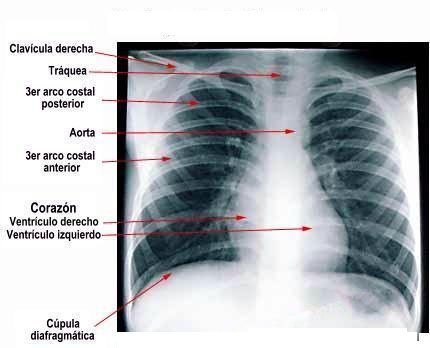

El tórax es la parte del cuerpo que está entre la base del cuello y el diafragma. Contiene a los pulmones, el corazón, a grandes vasos sanguínes como la arteria aorta y  la vena cava inferior, al esófago y al mediastino. Tiene la forma de cono truncado y su pared está formada por las costillas y los músuculos intercostales por los lados, que se unen por delante al hueso esternón y por detrás a la columna vertebral dorsal.